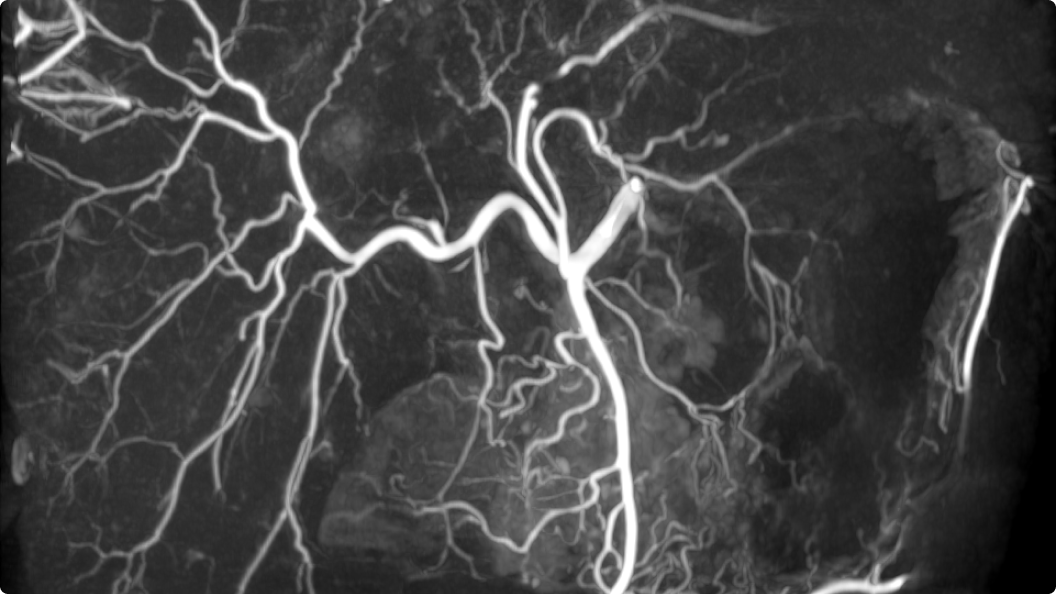

3D CT HD5

Optimierung von Diagnosen, chirurgischen Planungen, interventionellen Verfahren und Nachfolgeuntersuchungen

3D CT HD5 ist eine Option, die auf fortschrittlichen Algorithmen basiert. Diese Algorithmen verbessern die Visualisierung von Weichgewebe, reduzieren Rauschen und minimieren Artefakte, die den Visualisierungskomfort beeinträchtigen können. 3D CT HD bietet eine qualitativ hochwertige Bildgebung von internen Körperstrukturen einschließlich Gefäßen, Knochen und Weichgewebe. Mit dieser Funktion können Ärzte auf Aufnahmen von hoher Qualität zugreifen und fundierte Entscheidungen treffen.

3D CT HD5: Enhanced soft-tissue visualization and noise reduction for high-quality CBCT imaging